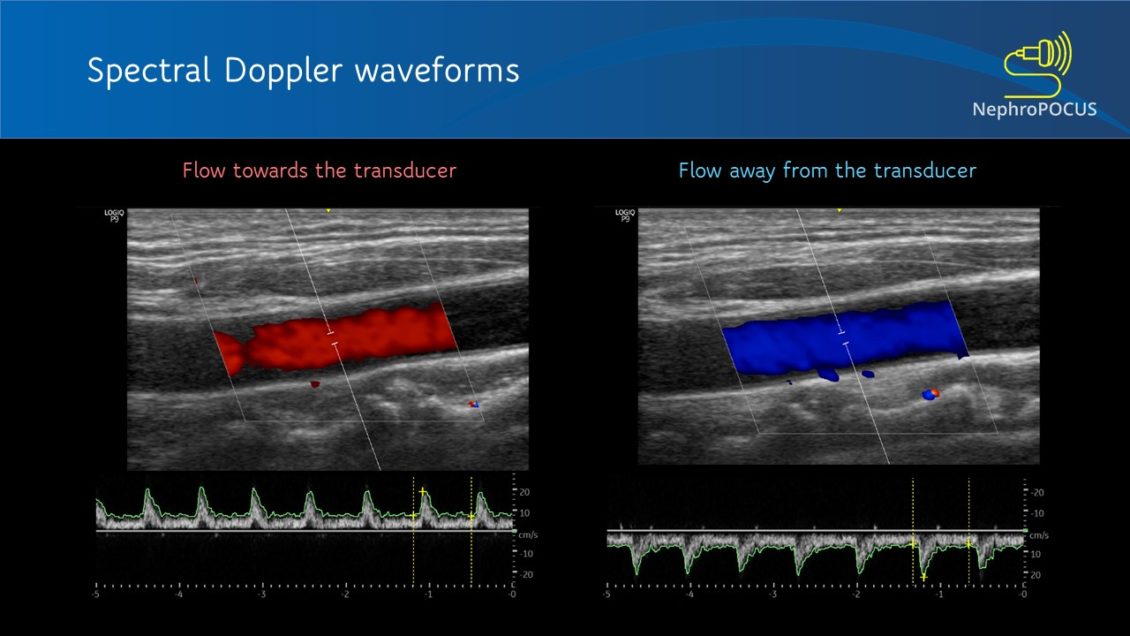

From www.renalfellow.org